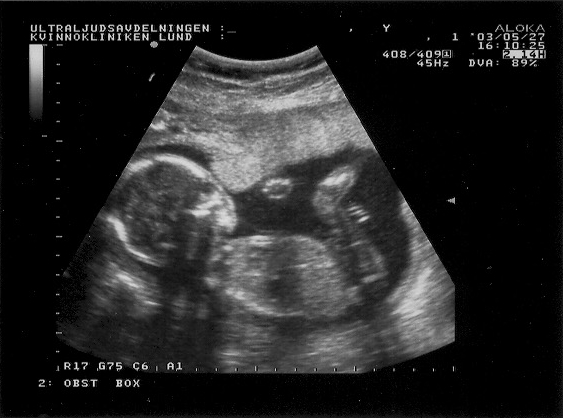

Ultra sound images from May 27, 2003.

The fetus is here 20cm tall and approx 20 weeks old.